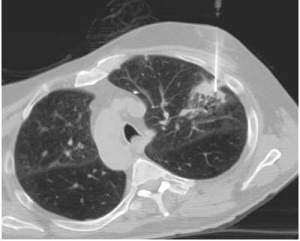

Kompjuterizovana tomografija CT - Može nam dati podatke

o poziciji tumora, veličini, invaziji torakalnog zida, zahvaćenosti medijastinalnih

limfnih čvorova. Magnentna rezonanca se preporučuje samo u pojedinim slučajevima

FNA (fine needle aspiration) - Uzimanje uzorka tumora

iglom kroz torakalni zid u lokalnoj anesteziji i pod kontrolom kompjuterizovana

tomografija CT. Ovakva metoda je manje invazivna u odnosu na otvorenu